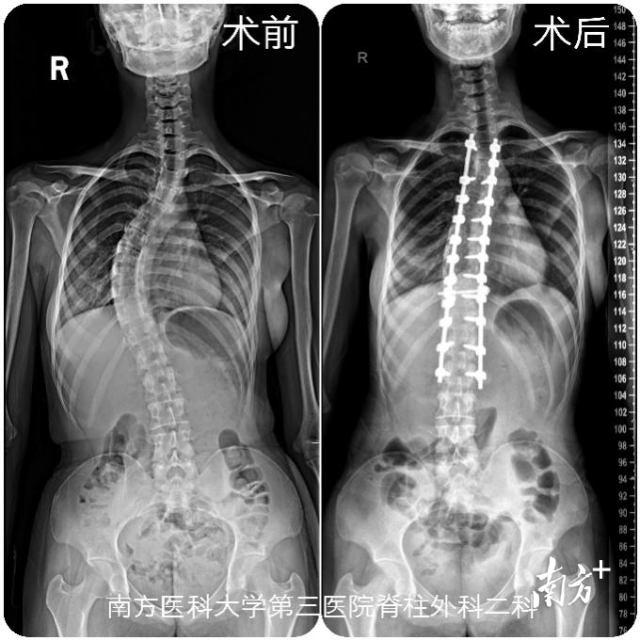

17岁的藏族少女达娃(化名),因双肩不平“剃刀背”被查出脊柱侧弯,在保守治疗无效的情况下,近日,达娃千里求医到广州南方医科大学第三附属医院。该院脊柱外科专家团队成功为达娃施行了脊柱侧弯矫形手术,术后效果良好,达娃“长高”了5厘米。

黎庆初团队经过详细讨论,慎重制定达娃的手术方案。完善术前准备后,黎庆初于8月31日为达娃行脊柱侧弯畸形矫正术,手术过程顺利。术后第五天,达娃佩戴支具下床活动,术前身高162cm,术后“长高”了5cm,达娃的家人非常高兴,感叹道:“终于可以放心了!”